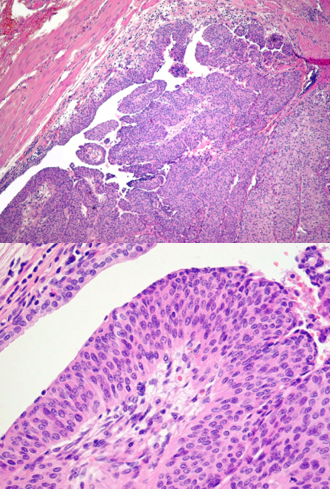

IDENTIFY

Urothelial (transitional cell) carcinoma (112)